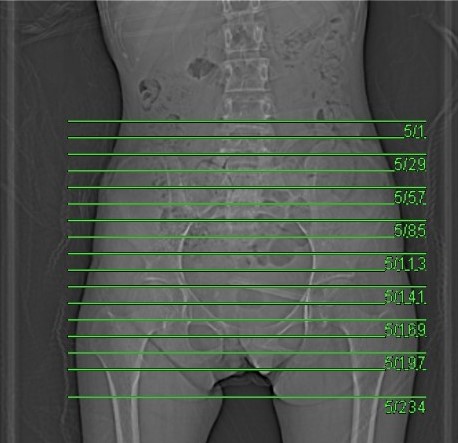

- Topogram

Topogram

- Position the patient in feet first supine position.

- Raise the patient’s arm above head to clear pelvis area.

- Align the patient’s body in Mid-Sagittal plane of the table (if possible).

- Internally rotate the patient’s legs (if possible).

- Position the transverse laser light beam at the level of 1 inch above iliac crest to start topogram.

Topogram Parameters

- Topogram length: 512Ā cm

- Slice: 0.6 mm

- Scanning direction: Craniocaudal

- Tube position: Top

- Stop the topogram scanning when the scanning reach / pass over the inferior pubis ramus / lesser trochanter.

- Plan the Scan FOV (SFOV) box at topogram image

- Set the top line at the level of 1 inch above iliac crest.

- Set the bottom line at the level of 1 inch below inferior pubic ramus / lesser trochanter.

- Ensure the lateral line to cover bilateral pelvis soft tissue.